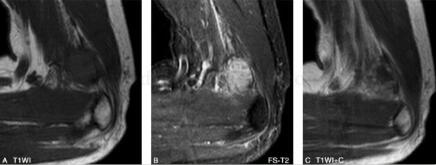

图3

(二)MRI

MRI能够直观地显示滑膜肉瘤的病灶形态、范围、与相邻关节、肌腱、滑膜及骨骼的关系。瘤体多表现为不规则,边缘呈分叶状,有时可见较清晰包膜。由于肿瘤常见囊变、出血、坏死以及钙化,因此MR信号不均。肿块内部的信号特点与其病理组织成分密切相关,T1WI上,肿块实体部分与周围肌肉信号相比表现为中等稍高信号,瘤体内的出血灶表现为点片状高信号,坏死或钙化区则表现为更低信号;

相应的T2WI上肿块实体部分表现为较高信号,坏死灶信号更高,钙化区表现为低信号,出血灶则信号不一,有时可见液-液平面;滑膜肉瘤较具特征性的MR表现是T2WI抑脂序列中,肿瘤表现为结节状稍高信号,结节呈大小近似的“卵石”状,其间有粗细不等的条状、网格状低信号间隔;增强扫描显示病灶不均一显著强化,病理证实系肿块内部含有丰富血窦。